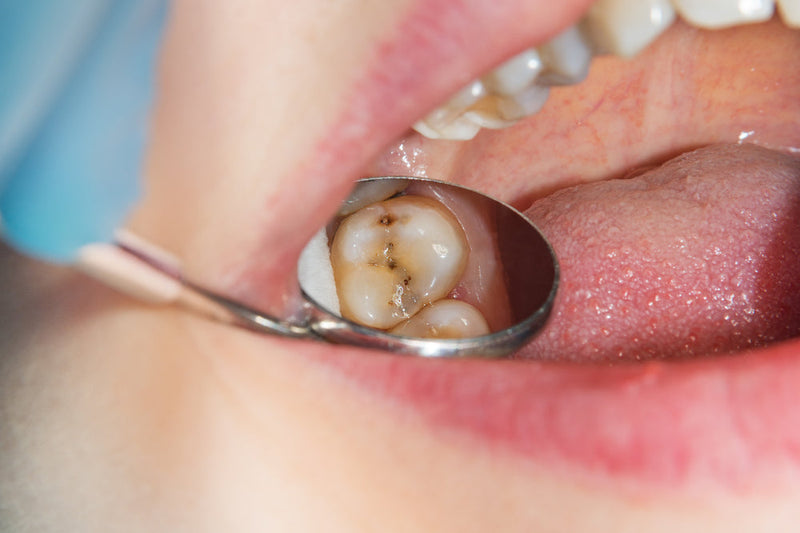

Today we're going to explore the world of cavities. Cavities, also known as dental caries, are areas of tooth decay that create holes in the teeth. They're often the result...